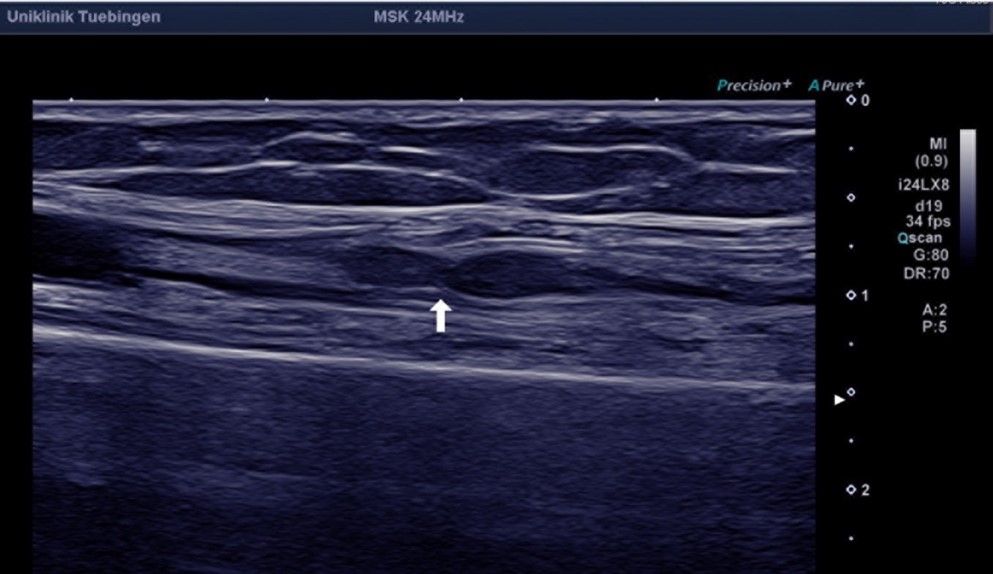

Die neuralgische Amyotrophie ist eine entzündliche Erkrankung, welche sich typischerweise durch plötzlich auftretende Schmerzen (häufig im Bereich der Schulter oder des Arms), gefolgt von einer Lähmung der Muskulatur, äußert. Eine Ursache ist nicht immer sofort erkennbar. Während die Schmerzen mit der Zeit abklingen, können die Lähmungen anhalten und infolge der Entzündungsreaktion narbige Einschnürungen an den betroffenen Nerven entstehen. Die Erkennung dieser Einschnürungen („Konstriktionen“) kann zunächst schwierig sein und erfordert spezielle Untersuchungsmethoden im Sinne einer hochauflösenden Neurosonographie durch erfahrene Neurolog*innen oder einer MR-Neurographie. Sollten sich solche Nervenkonstriktionen bestätigen kann eine operative Therapie gute Ergebnisse erzielen.

Ein lange Zeit weitgehend unbekanntes und weiterhin unterdiagnostiziertes Krankheitsbild stellt die neuralgische Amyotrophie, früher auch Plexusneuritis oder Schulteramyotrophie, dar. Hierbei handelt es sich um eine entzündliche Nervenerkrankung, deren Ursache nicht immer geklärt werden kann. Risikofaktoren stellen eine übermäßige mechanische Beanspruchung (z.B. durch ungewohnte starke körperliche Aktivität), immunologische Auslöser (z.B. Infektionen) oder eine genetische Veranlagung dar. Durch Verbesserungen in der Diagnostik, insbesondere dem hochauflösenden Nervenultraschall sowie der Magnetresonanzneurographie gelingt eine zunehmend bessere bildgebende Darstellung des gesamten Verlaufs peripherer Nerven. Dabei können einerseits entzündlich bedingte Schwellungen der Nerven festgestellt und die Diagnose bestätigt werden.

Die neurologische Akutbehandlung besteht aus schmerzstillenden Mitteln sowie hochdosierten entzündungshemmenden Cortison-Infusionen mit. Häufig bilden sich die Beschwerden darunter nach einigen Wochen wieder zurück. Immer wieder kommt es jedoch zu einem Fortbestehen der Lähmungen. Mithilfe der oben genannten Fortschritte bei bildgebenden Untersuchungen zeigte sich in den letzten Jahren, dass bei diesen Patientinnen und Patienten häufig narbige Einschnürungen der betroffenen Nerven bestehen, (sogenannte uhrglasförmige Nervenkonstriktionen), die den Nerv sogar verdreht erscheinen lassen können („Torsionen“). Bei Vorhandensein solcher Konstriktionen ist in der Regel eine medikamentöse Behandlung nicht weiter erfolgversprechend. Durch eine operative Narbenlösung kann dann in der Regel eine gute Erholung der Nervenfunktionen erreicht werden.

In der Regel sind weitergehende Untersuchungen in Form von elektrophysiologischen Messungen (Neurographie, Elektromyographie) und bildgebenden Darstellungen des betroffenen Nervs mittels hochauflösenden Ultraschalls (Sonographie) oder Kernspintomographie (MRT) notwendig.